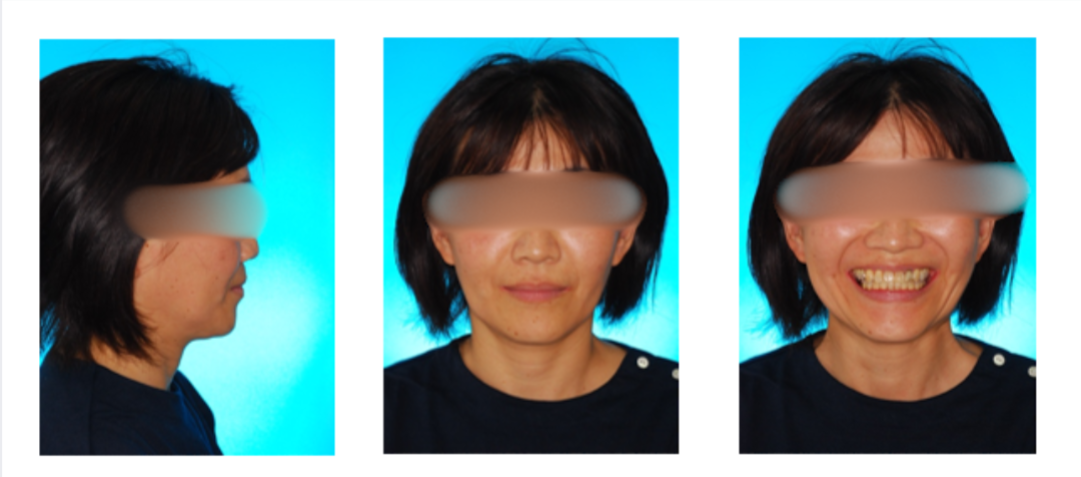

反対咬合の症例

初診時

治療終了時

治療終了から3年経過時

(保定開始から3年経過時)

初診

治療終了時

治療終了後から3年経過時

(保定開始時から3年経過時)

| 年齢・性別 |

40代 女性 |

| 主訴 |

前歯の咬み合わせが逆になっているのを治したい。 |

| 治療について |

非抜歯にて治療を行い、内側に傾斜している上の前歯を前方に移動させました。 |

| 注意点・リスク |

| 治療期間 |

2年1ヶ月 |

| 治療費用 |

1,222,100(検査料と診断料、全ての調整料を含む) |

| 治療に用いた主な装置 |

マルチブラケット装置(上顎舌側、下顎唇側の装置) |

| 抜歯部位 |

無し |

| 通院回数 |

21回 |